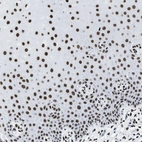

Immunohistochemical staining of human cerebral cortex shows strong nuclear positivity in glial cells.